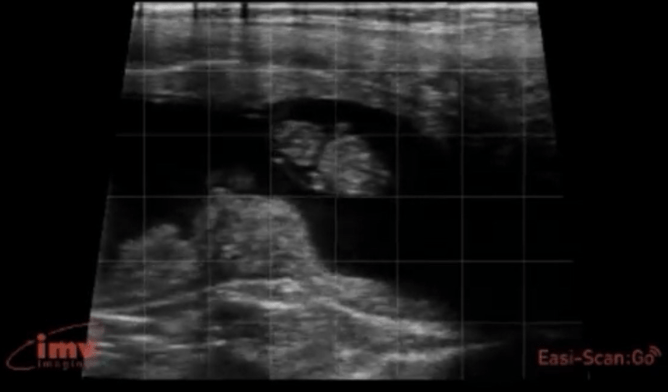

Our view of a calf foetus at various gestation stages: